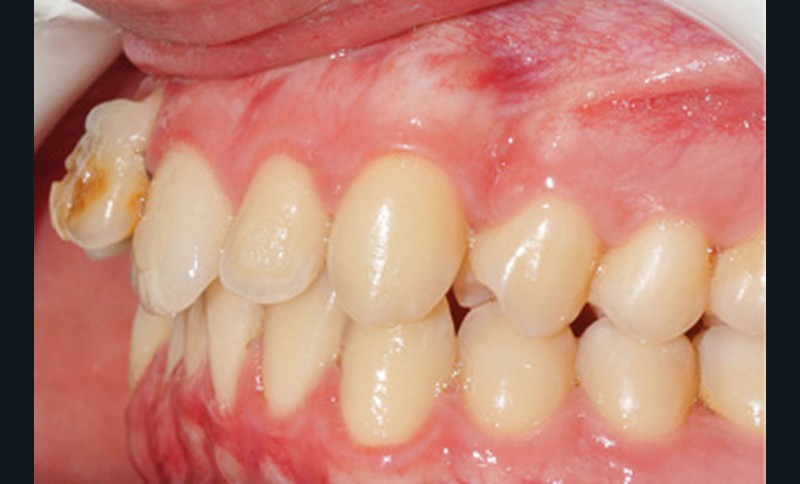

D’un point de vue occlusal, le patient, en denture adulte jeune stable, présente une classe II d’Angle bilatérale de 4 mm, associée à un encombrement maxillaire de 5 mm et mandibulaire de 2 mm. La face mésiale de 21 est centrée avec le plan sagittal médian, la non-concordance des médianes incisives est d’origine mandibulaire (déviation de la médiane mandibulaire vers la gauche) (fig. 1b-d).

Son incisive centrale supérieure droite (11) présente un défaut de structure amélaire sévère, compromettant une technique restaurative pérenne a minima. L’examen de la panoramique (fig. 1e) et de la radiographie rétroalvéolaire de 11 (fig. 1f) objective une fracture coronaire verticale, ainsi qu’une racine grêle et courbe, peut-être en rapport avec un ancien traumatisme [1]. Le rapport couronne clinique/racine clinique est défavorable.